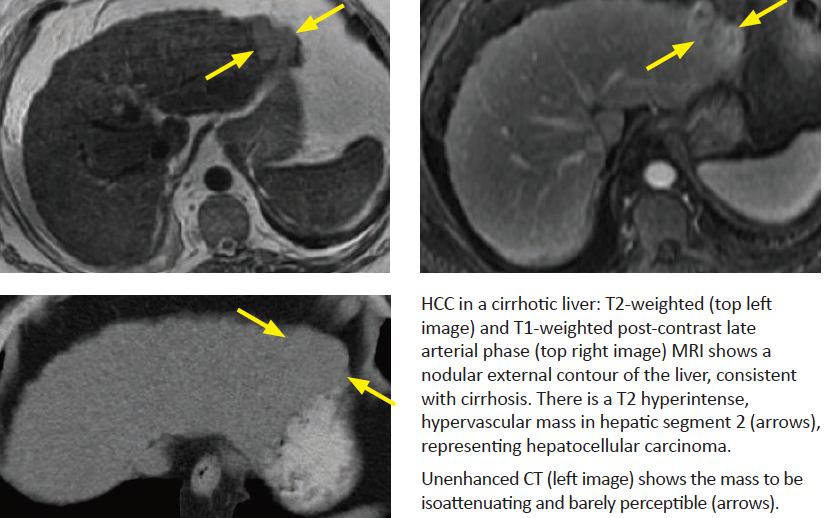

HCC

Major risk factor?

HCC is the diagnsosis until proven otherwise in what scenario?

What tumor marker is elevated and in what percent?

What is the characteristic imaging feature and how often does this occur?

Classic CT or MRI appearance?

What does a nodule in nodule appearance represent?

HCC tends to do what locally? Contrast this with mets?

Treatment options?